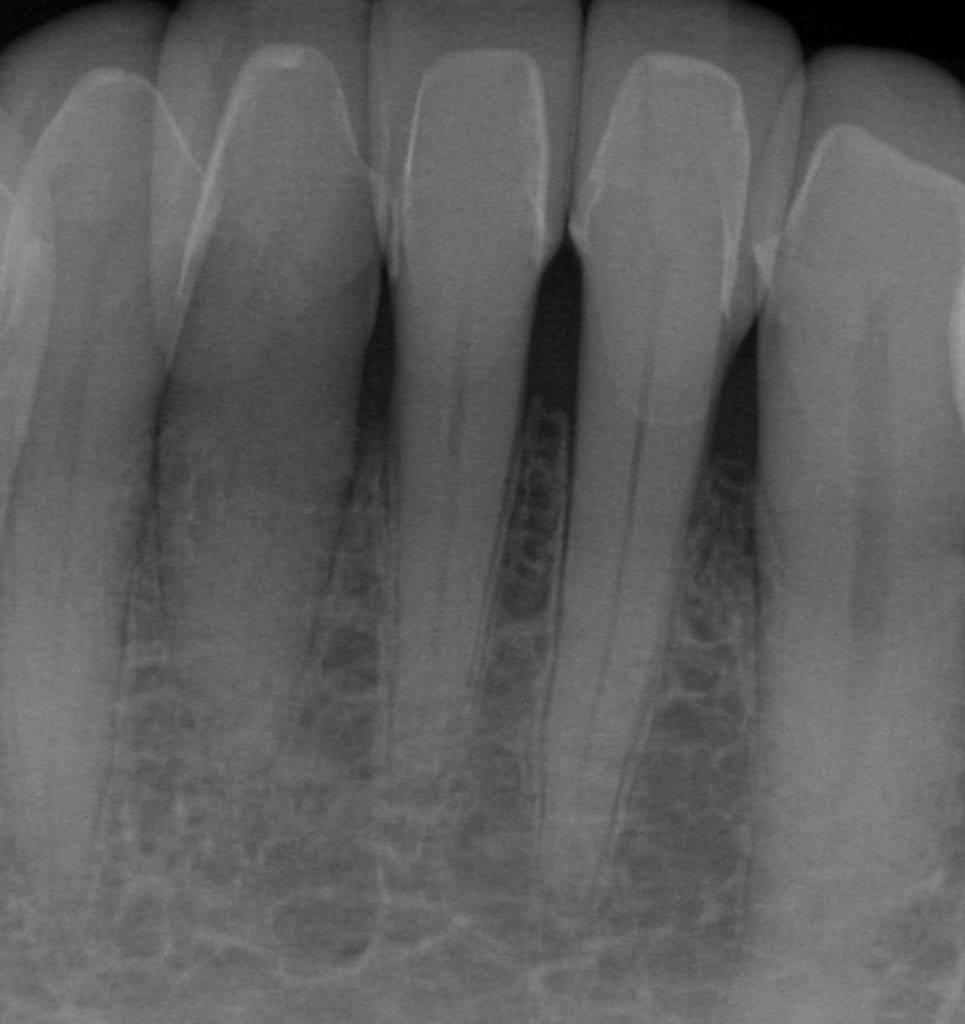

Pre-existing restorations that warranted replacement with an increase in vertical dimension.

Pre-existing restorations that warranted replacement with an increase in vertical dimension. The upper and lower arch were captured with the medit I500 and articulated together with enough clearance to accommodate new restorations and to restore the patient to an ideal tooth position.

ONE WEEK POST-OP RADIOGRAPHS / CEMENT CHECK